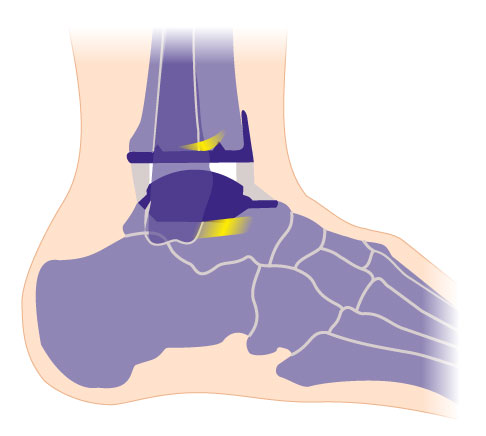

Bei den individualisierten TEP (Totalendoprothesen) für das Sprunggelenk werden sowohl das Sprungbein (Talus) als auch die Schienbeingelenkfläche (Tibiagelenkfläche) mit einer Metallkappe überzogen. Die Rückflächen der Kappen sind titanbestrahlt und mit Hydroxylapatit beschichtet und gehen während des Heilungsprozesses eine stabilen Verbindung mit dem natürliche Knochen ein.

Die dritte Komponente der Prothese ist ein frei beweglicher Polyethylen-Gleitkern, der die wichtige Bewegung zwischen den beiden Gelenkpartnern vermittelt. Die freie Beweglichkeit des Gleitkernes ermöglicht eine uneingeschränkte Belastung der Prothesenflächen. Die Kunststoffkerne wurden in den letzten Jahren optimiert. Sie sind härter und bewirken eine bessere Quervernetzung des Polyethylens.

Die Sprunggelenksprothese (OSG-TEP) wird nach genauer Anpassung durch Probeimplantate und Kontrolle der Lage zementfrei eingesetzt. Der Spezialist verklemmt die Originalkomponenten der Prothese am Knochen. Durch die sorgfältige Präparation der knöchernen Struktur können sich die Implantate nicht mehr verschieben.

Die Sprungbeinkomponente wird primär durch beschichtete Führungsbolzen am Knochen fixiert, sogenannte Press-Fit-Zapfen. Die Scheinbeinkomponente überzieht die Knochenfläche der Tibia. Die Rückseite hat je nach Prothesentyp kleine Dorne für die knöcherne Fixierung.

Beide Komponenten des Sprunggelenkersatzes sind auf der am Knochen anliegenden Seite mit einer speziellen Hydroxylapatit-Beschichtung überzogen und mit Titan bestrahlt, um ein sicheres Einwachsen des Knochens zu erreichen.

Die dritte Komponente der individualisierten 3-Komponenten-Sprunggelenksprothese ist ein frei beweglicher Kunststoffgleitkern aus Polyethylen, der die Bewegung zwischen den beiden Gelenkpartnern vermittelt. Der Gleitkern hat eine quaderförmige Form.